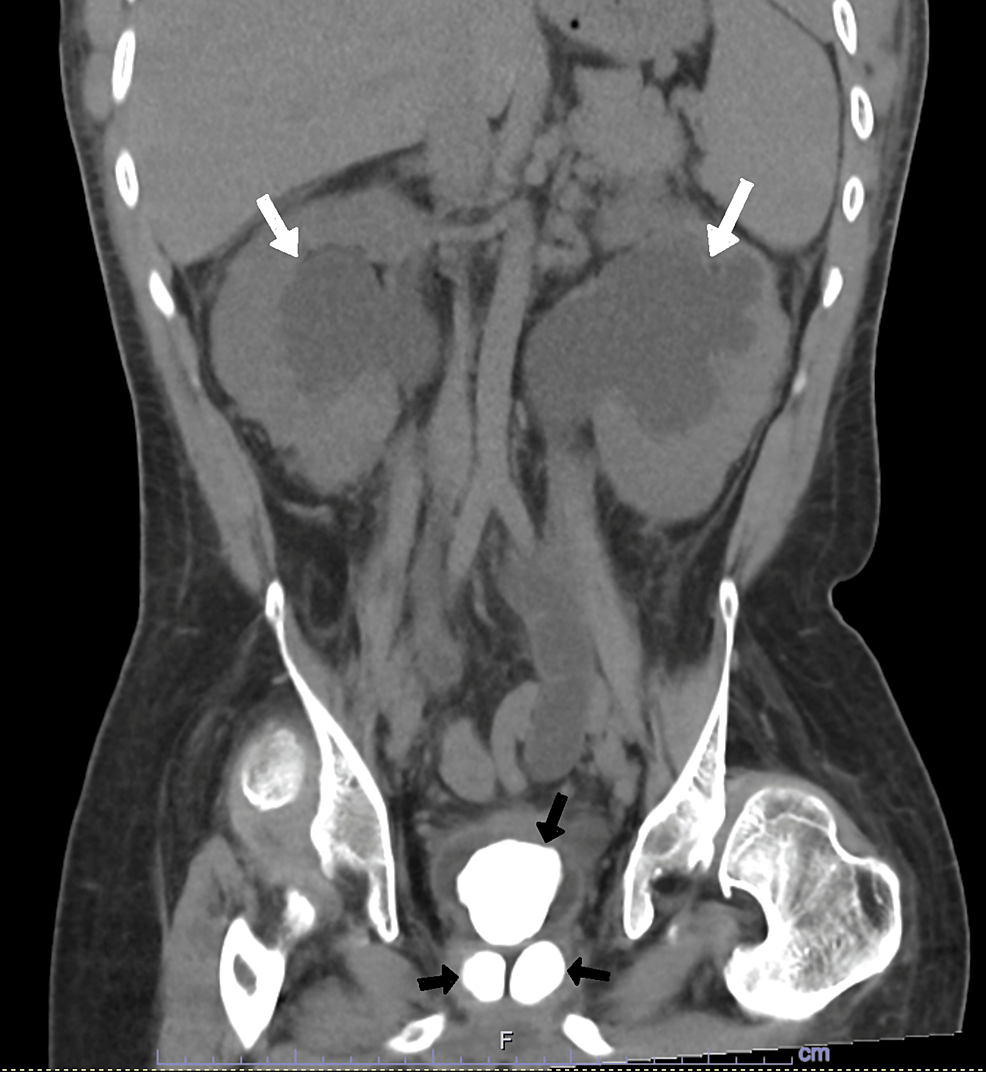

Computed tomographic scan of bladder stones. Figure 2. Bladder stone Radiopaque Bladder Stones In general, us is poor at localizing ureteral stones, especially in the absence of. If kidney, ureter, and bladder radiographs fail to depict the stone, ct may be needed to follow its passage. This article reviews types of urinary calculi and their imaging appearances, presents direct and secondary imaging findings of urolithiasis, and provides an. Urethral obstruction in males is. Radiopaque Bladder Stones.

a. Noncontrast CT A&PLarge bladder stone with severe right Radiopaque Bladder Stones Stones are most easily identified in the kidney and in the distended urinary bladder (fig. This article reviews types of urinary calculi and their imaging appearances, presents direct and secondary imaging findings of urolithiasis, and provides an. Urethral obstruction in males is the most common presenting problem, but signs similar to those associated with other types of uroliths also may. Radiopaque Bladder Stones.